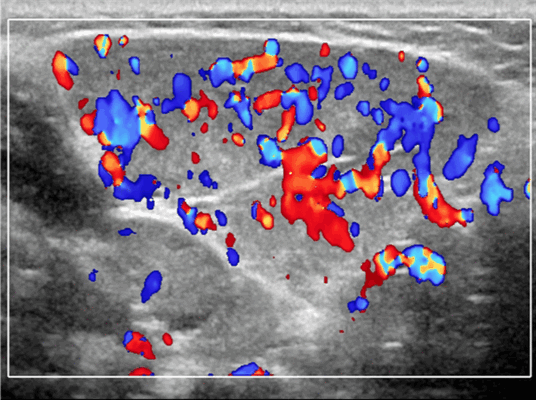

Ультразвуковая визуализация слюнной железы. Общие особенности

Лучший диагностический критерий. Неоднородно гипоэхогенное поражение, синусоидальные сосудистые пространства, движение вперед и назад в реальном времени ± эхогенные флеболиты. Выраженный сигнал потока на цветном или энергетическом доплеровском режиме. Монофазный низкоскоростной поток на импульсном доплеровском режиме

Результаты ультразвукового исследования. УЗИ в серошкальном режиме. Большинство сосудистых венозных гемангиом (80%) выглядят неоднородно гипоэхогенными. Большие анэхогенные сосудистые пространства видны менее чем в 50% случаев, серпигинозные и синусоидальные. Поражения с небольшими сосудистыми каналами могут казаться эхогенными (из-за множества акустических границ, отражающих звук). Определить пределы образования бывает трудно, так как компоненты поражения могут быть изоэхогенными в околоушной паренхиме и незаметно смешиваться. Внутрипросветное движение эхо-сигналов при УЗИ в реальном времени, представляющее медленный сосудистый кровоток. Характерны эхогенные флеболиты с задним акустическим затенением. Сообщается, что они присутствуют только в 20% ВСМ. Иногда поражается вся околоушная железа, имитируя диффузную или инфильтративную патологию. Целесообразность склеротерапии оценивается соотношением сосудистых пространств к эхогенной матрице

Импульсный допплер. Монофазный, низкоскоростной поток может иногда обнаруживаться в анэхогенных и гипоэхогенных пространствах, представляющих открытые сосуды со значительным кровотоком. Отсутствие допплеровского сигнала при медленном кровотоке или тромбировании

Цветной допплер. Выраженный цветной доплеровский сигнал присутствует в областях, где поток значительный. Используйте фильтр для стенок сосудов и низкую частоту повторения импульсов (PRF) для увеличения доплеровской чувствительности. Отсутствует допплеровский сигнал при медленном кровотоке или тромбировании. Доплеровский сигнал потока изменяется различными маневрами. В поверхностных участках доплеровский сигнал может быть остановлен прямым сжатием датчика над поражением. Сигнал потока может иногда быть усилен маневром Вальсальвы или дистальным сжатием, но последнее трудно выполнить в области лица.